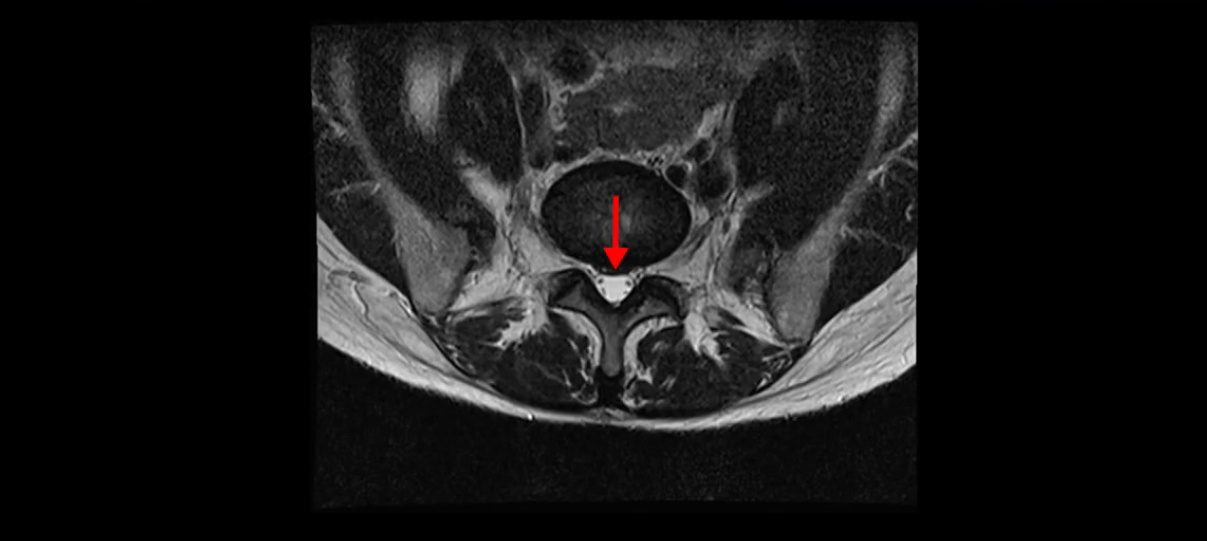

그리고 만약에 이 디스크가 급성으로 찢어진 것이라면 아주 심한 디스크성 통증이 있겠죠. 기침이나 재채기를 하면 심하게 아프고 허리를 조금만 구부려도 아주 날카로운 통증들이 생길 겁니다. 그런데 이분은 이런 증상이 전혀 아닙니다. 디스크의 돌출 정도와 협착이 전혀 심하지 않기 때문에 이분이 가지고 계신 양쪽 다리 저림, 특히 이분은 누워있을 때도 양쪽 다리가 저리다고 하는데, 디스크 때문에 그런 증상은 생길 수가 없습니다. 또 이 디스크는 오래된 디스크, 이미 찢어진 섬유륜이 아문 디스크이고, 그러니까 이분은 기침이나 재채기를 못하는 증상이 없는 거죠. 그 다음에 허리를 구부릴 때 뻐근한 증상은 있지만 아주 날카로운 통증은 없습니다.

이처럼 이분의 가벼운 디스크 탈출은 이미 오래 전에 진행되었고 섬유륜 자체는 이미 아문 상태인데도 디스크내장증을 진단받은 환자들 중에는 본인이 섬유륜 파열 환자라고 끝까지 믿는 분들이 많습니다. 다시 말하지만 디스크내장증이라는 진단을 받은 환자들 거의 대부분 섬유륜 파열 증상이 아닙니다. 진단이 잘못되면 어떤 치료를 받아도 좋아질 수 없습니다. 그럼 이분은 다른 여러 병원에서 어떤 얘기들을 들었을까요?

이분 MRI를 보시면 퇴행성디스크가 있고 약간의 협착이 있지만 이 정도의 퇴행성디스크와 협착으로는 신경이 눌려서 양쪽 다리가 저리고 아픈 증상이 나올 수가 없습니다. 그래서 MRI와 이 환자분의 다리 증상이 매치가 안 된다고 하는 의사들이 많은 겁니다.